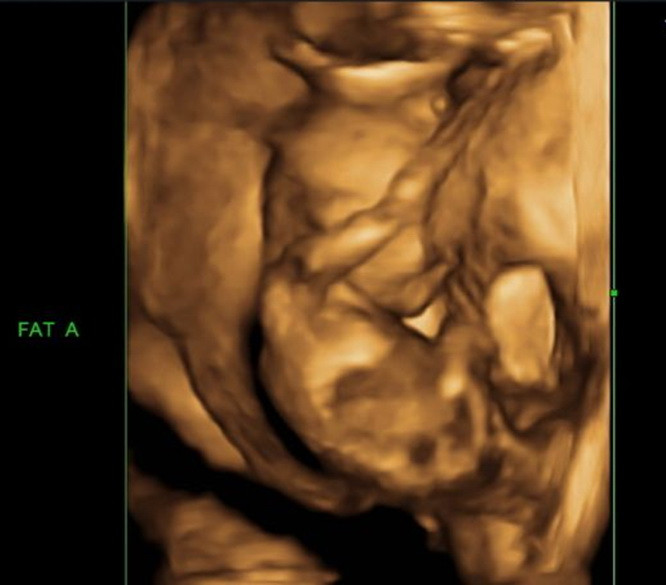

O femeie din Mexic a ramas fara cuvinte dupa ce medicii i-au aratat la ecograf ce poarta in pantece.

O femeie din Mexic este insarcinata cu noua bebelusi - sase fete si trei baieti - a anuntat in noaptea de joi spre vineri postul de televiziune Televisa, citat de Reuters.

Femeia este internata intr-un spital din Saltillo, principalul oras din statul Coahuila. Karla Vanessa Perez, a carei varsta nu a fost precizata, a urmat un tratament care a condus la aparitia acestei sarcini multiple.

Agentia de presa mexicana Notimex a confirmat, la randul ei, aceasta sarcina speciala si a spus ca Perez va naste pe 20 mai.

Aducerea pe lume cu succes a noua copii de catre aceeasi mama, in aceeasi zi, ar reprezenta una dintre cele mai spectaculoase nasteri multiple care s-au inregistrat vreodata.